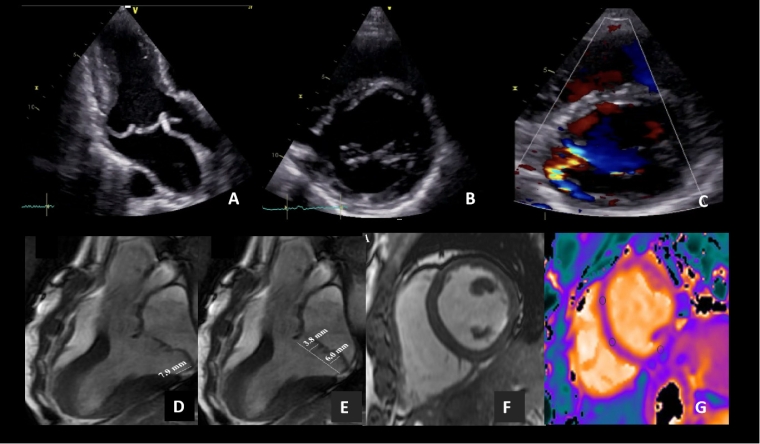

Figure 5. Multimodality imaging of a 46-yo-female air race pilot that in a routine PPCE was found to have an end-systolic heart murmur. A) Parasternal TTE long-axis view showed a myxomatous mitral valve prolapse with bileaflet involvement. B and C) Parasternal TTE short-axis view showed a complex mitral jet that was considered of moderate degree (video available in 5.1..). A CMR was indicated for risk stratification purposes which showed positive mitral annular disjunction, bilateral mitral valve prolapse (E) and no other SCD-associated features: F) No LGE was detected and G) Native T1 values were normal.